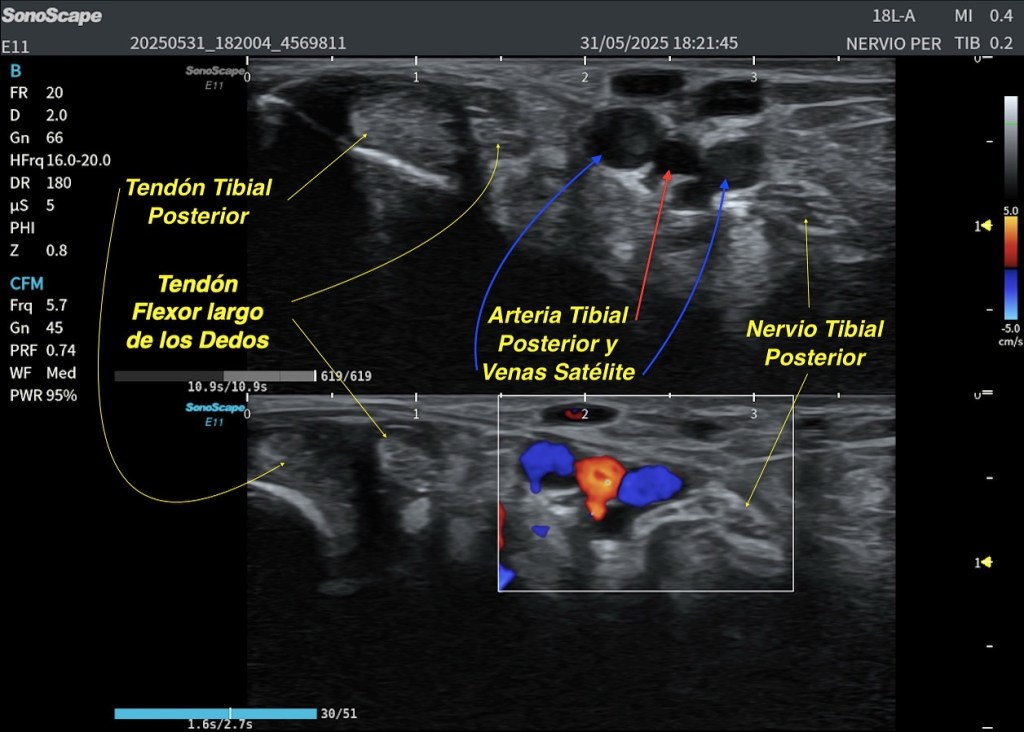

En esta imagen ecográfica observamos una exploración transversal a nivel del tobillo, enfocada en la región del nervio tibial posterior, una zona clave en el diagnóstico de neuropatías y síndromes compresivos como el síndrome del túnel tarsiano.

Tendón Tibial Posterior: Ubicado medialmente, importante en la estabilidad del pie. Tendón Flexor Largo de los Dedos: Acompaña al tendón tibial posterior en su recorrido por la cara interna del tobillo. Arteria Tibial Posterior y Venas Satélite: Visualizadas con Doppler color, fundamentales en la valoración vascular. Nervio Tibial: De aspecto hiperecoico, adyacente a los vasos, objetivo principal en estudios neurológicos.

Sonda: Lineal de alta frecuencia (18L). Modo Doppler Color para localización y análisis vascular. Profundidad y ganancia ajustadas para resaltar estructuras neurovasculares.